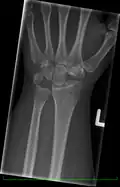

Left hand x-ray with Kienbock's Disease -